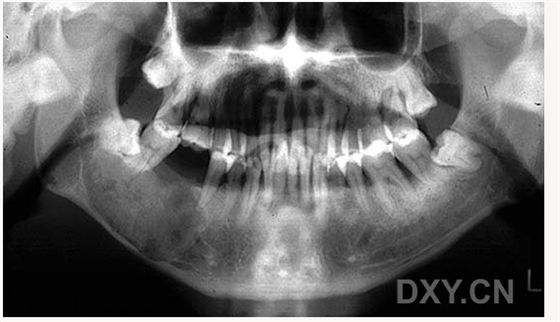

大理石骨?。ㄏ骂M骨有明顯的骨化影像,恒牙埋伏)